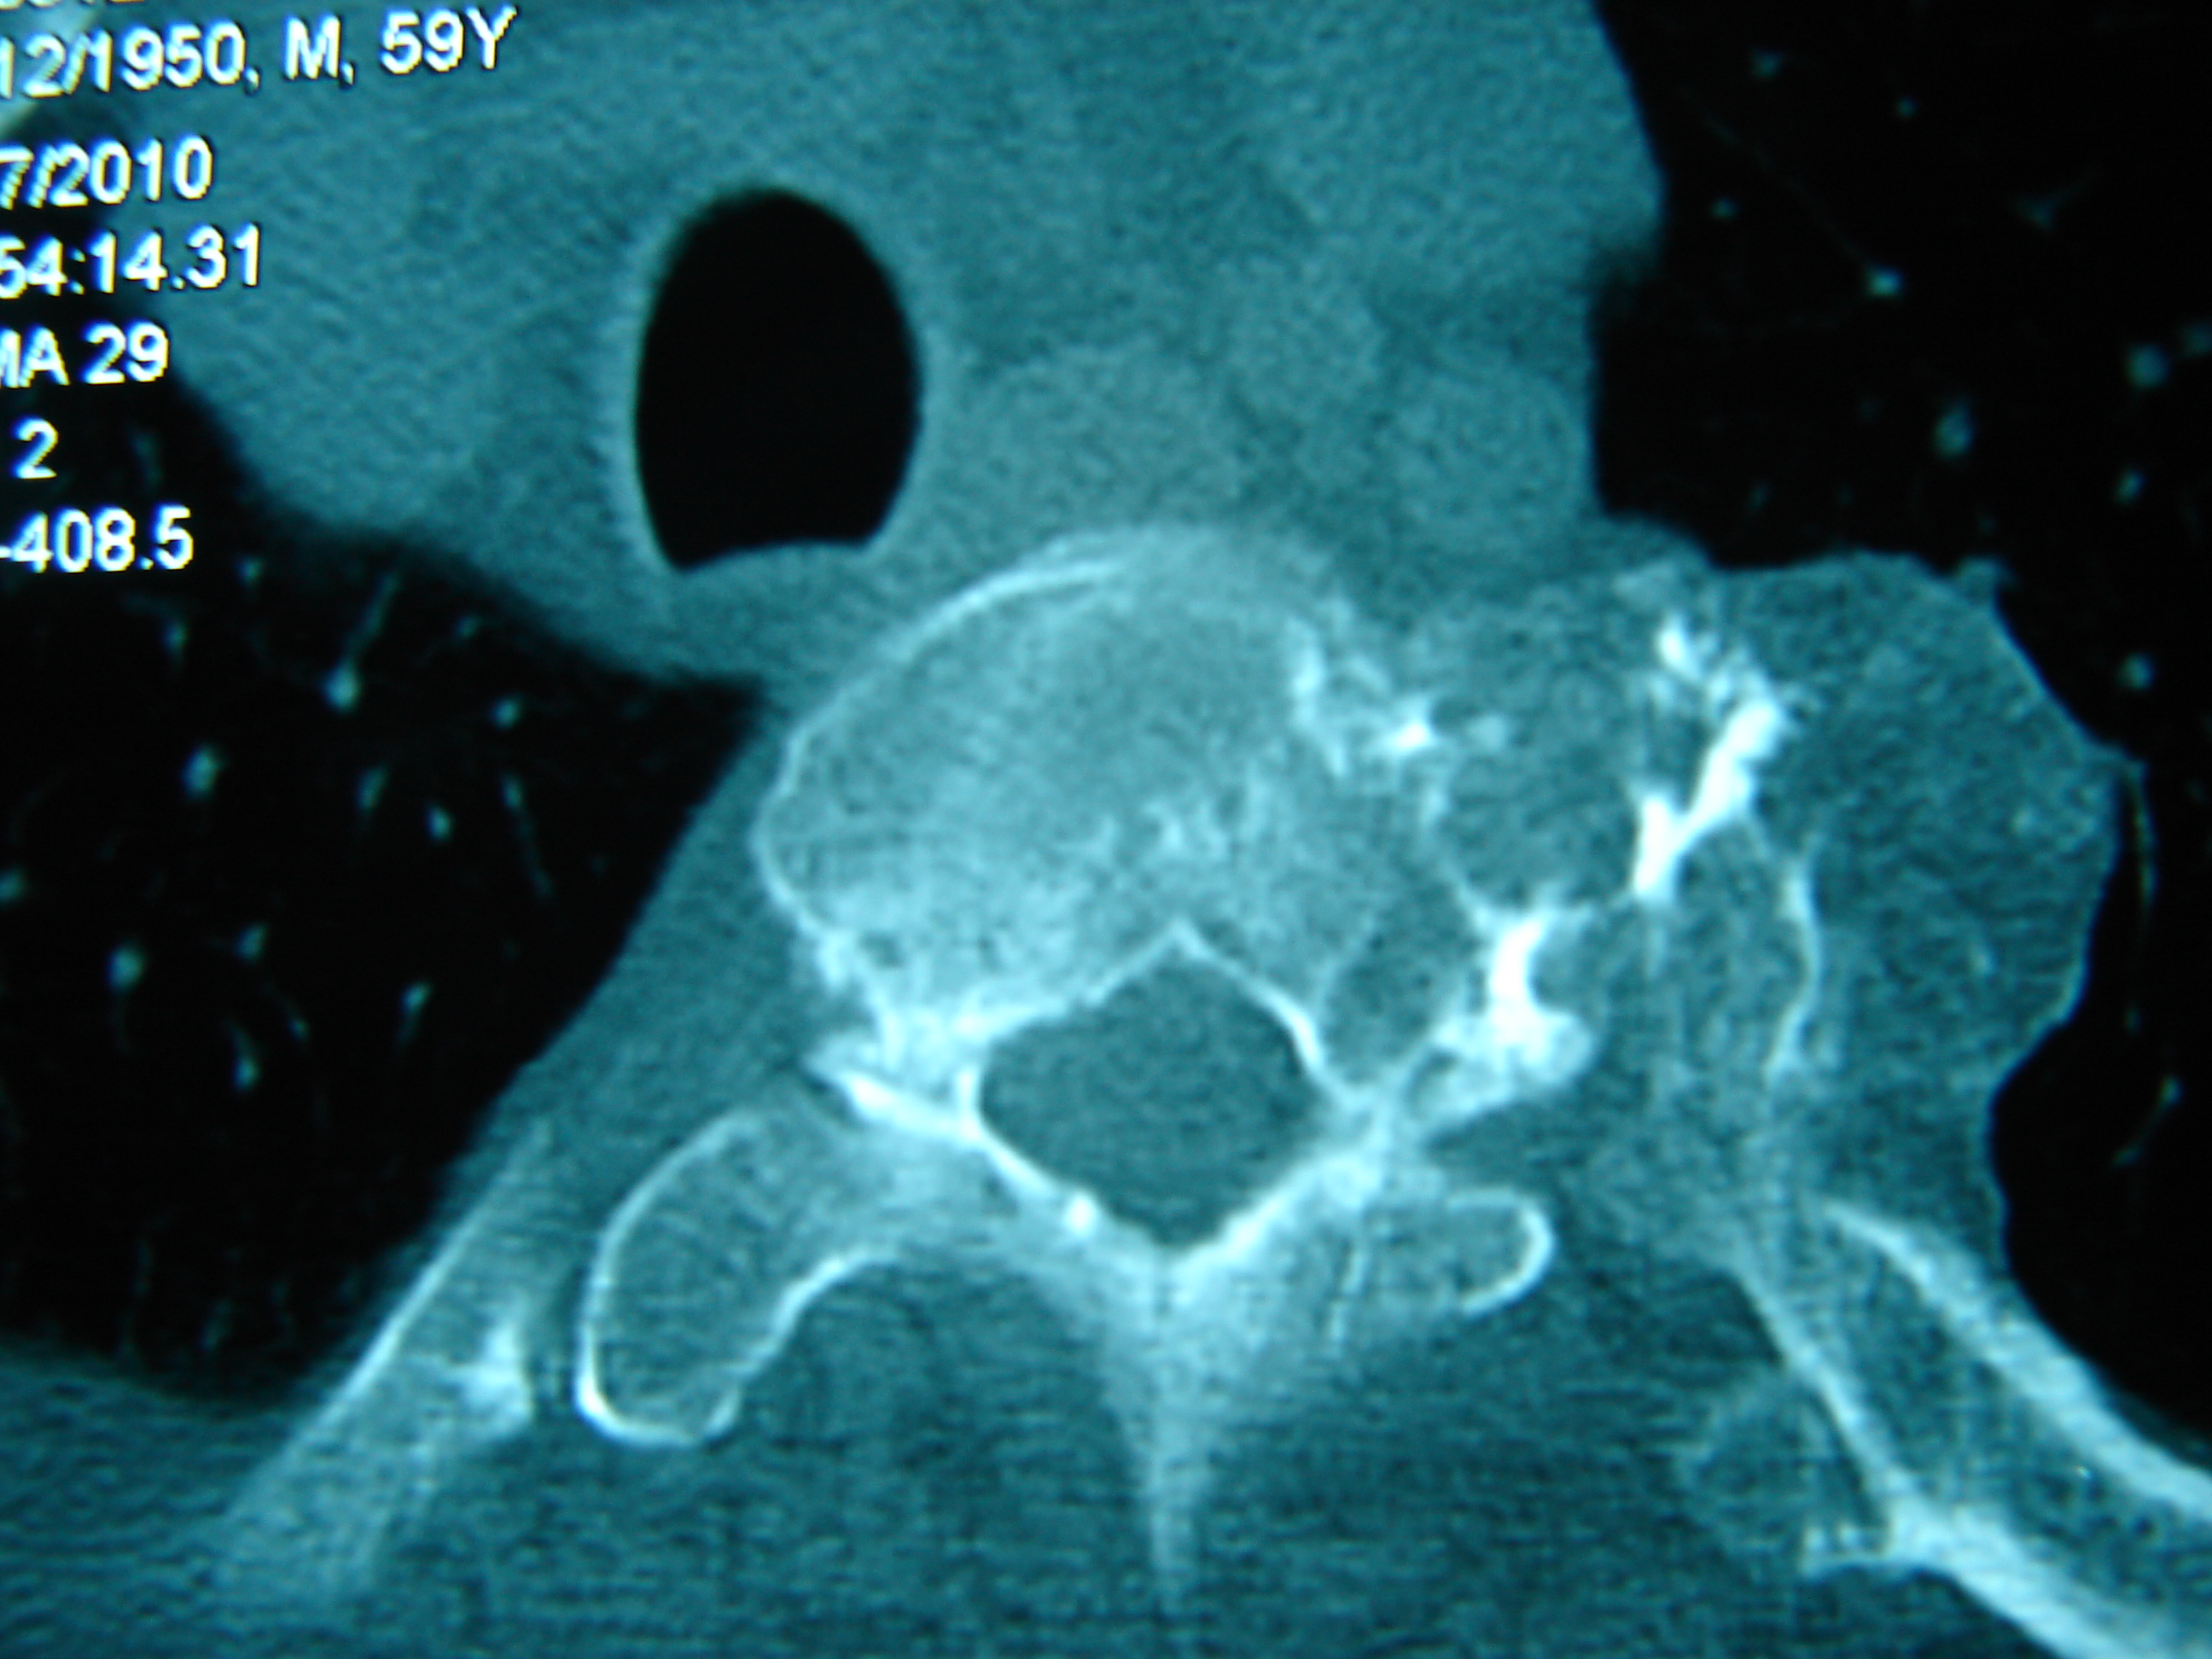

Εικόνα 3 α,β,γ,δ,ε,ζ

Μαγνητική τομογραφία (εγκάρσια – αξονική λήψη) Τ1 και Τ2

Παρατηρείται η επέκταση του καρκίνου εντός του σπονδυλικού σωλήνα και προς τα αριστερά εκτός του σπονδυλικού σώματος, προκαλώντας απώθηση της κατιούσης αορτής.